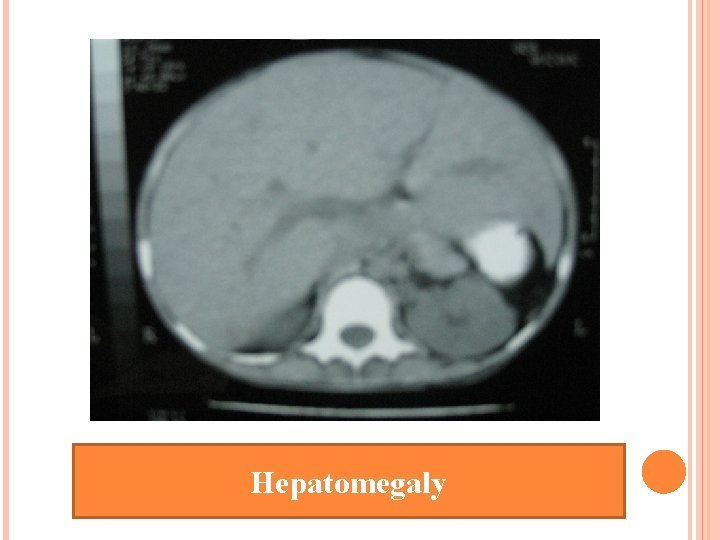

Ultrasound whole abdomen : diffuse hepatomegaly

Hepatomegaly